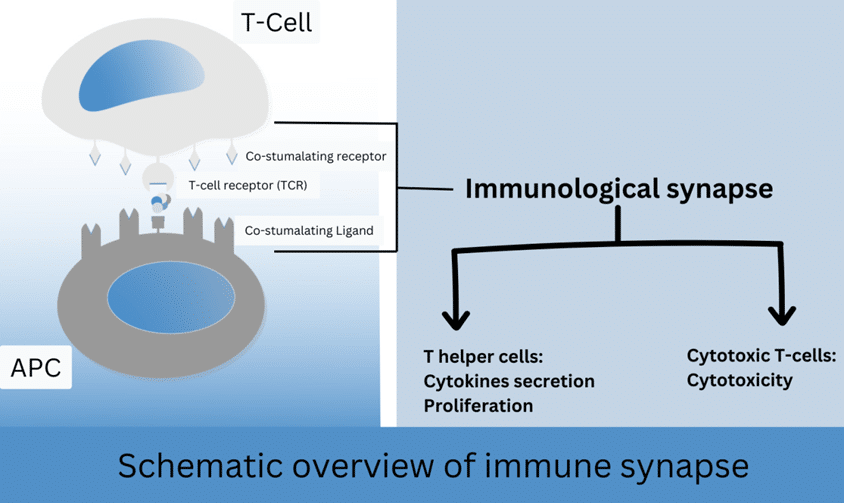

The Role of Immunity in Neurodegenerative Disease: A Literature Review

Neurodegenerative diseases such as Alzheimer’s disease, parkinson’s disease, and multiple sclerosis are increasing over the period. The cause of neurological...Read More